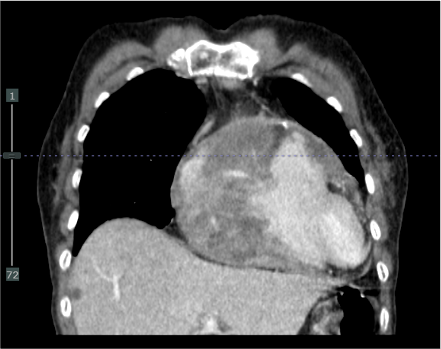

Echocardiogram accidentally found large anterior heterogeneous mass sized about 5x7 cm. This mass adjacent to right atrium (RA), right ventricle (RV) and tricuspid annulus causing mild to moderate tricuspid regurgitation (TR), no pericardial effusion. Chest CT was requested, reporting irregular-shaped heterogeneous anterior mediastinal mass sized 6.7x9x4.7 cm involving tricuspid valve, anterior wall of RA and RV. Right coronary artery (RCA) also passed through this mass.